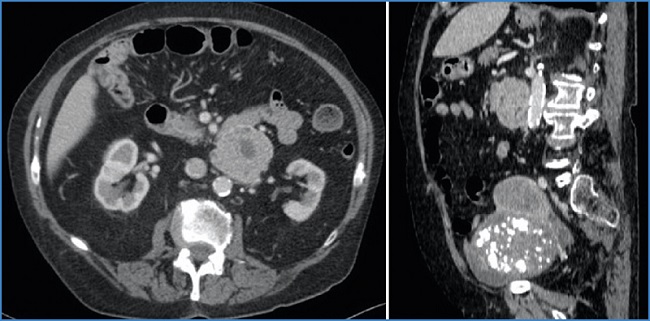

En el estudio preoperatorio de la neoplasia ginecológica se realiza una tomografía axial computarizada (TAC) abdominotorácica pélvica que identifica una masa retroperitoneal (Fig. 1).

Figura 1. TAC: masa retroperitoneal de 7 cm de diámetro, hipervascular, con áreas quísticas-necróticas, bien delimitada, en contacto con la cuarta porción duodenal y la aorta infrarrenal.